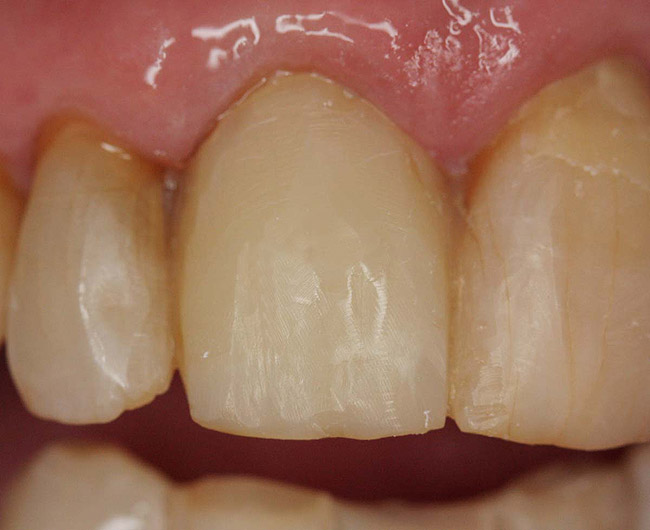

Figure 12  Endodontically treated mandibular central incisors that require only restoration of endodontic access holes with composite.

Figure 12

Figure 13  Access holes after endodontic treatment.

Figure 13

Figure 14  Final restoration with bonded composite.

Figure 14

Case 3

Class IC mandibular central incisors had extensive amounts of tooth structure remaining following endodontic treatment (Figure 12 and Figure 13). Restoration of the access holes was completed with bonded composite (Figure 14).